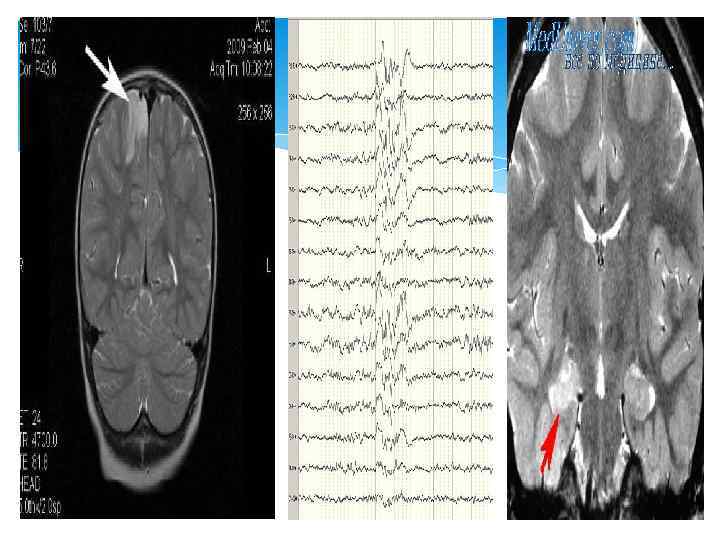

Диагностикасы: Электроэнцефалографиялық зерттеу Компьютерлік томография немесе МРТ Нейросонография Бас миының қан тамырларының допплерографиясы

Клиникасында негізгі триада: Инфантильді спазмдар(аксиальды бұлшық еттер тобының жиырылуы) Психоматорлы бұзылыстар Гипсаритмия(жоғары амплитудалы, асинхронд ы, диффузды, белсенділігі жай толқынды тета және дельталар)

Синдром Уэста-емшек жасындағы балаларда жиі кездеседі(4 -9 айлық жаста) және орталықтанған денесіндегі, аяғындағы құрысулармен жүреді. Ауру ұстамасы бір күнде бірнеше рет(кейде 50 -ге дейін) қайталанады. Ұстама жиі бала ұйықтап жатқанда болады. Синдром Янца-кездесу жиілігі 8% ден 10% аралығында 5 жастан 16 жасқа дейінгі балалар ауырады. Миоклоникалық ұстамалар басымырақ. Ұстама бала оянғаннан соң 15 -30 минуттан соң пады болады.